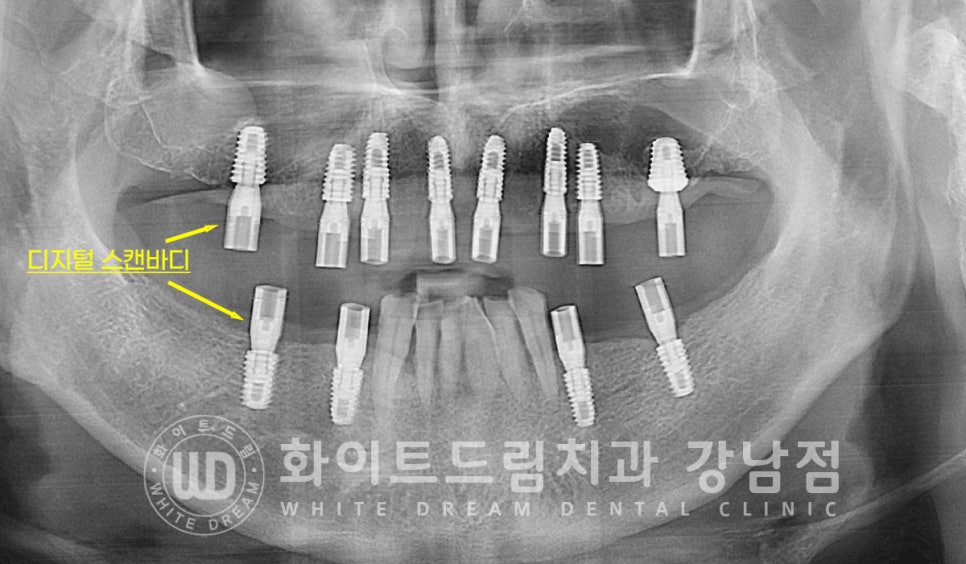

꼭 네비게이션 임플란트처럼 비용이 추가되는 디지털 방식을 사용해야만

임플란트 수술 범위를 줄일 수 있는 것은 아니랍니다. ^^

의료진의 숙련도에 따라서 이렇게 절개범위가 적게 임플란트를 식립하는 것도 가능하죠.

이 모든 수술 과정은 저희 강남 화이트드림치과의 정수윤 대표원장님이 직접 진행하셨습니다.

저희 강남 화이트드림치과에서는 임플란트 인상 채득 과정도 불편한 고무인상재를 사용하지 않고

5분 안에 전악 스캔이 가능한 3D 구강 스캐너를 이용하여 진행하고 있답니다.

디지털 스캔으로 편안하게 구강 데이터를 확보하게 되면

이 데이터가 바로 원내 기공실로 전송되며, 원내 기공실에서 최종 보철을 디자인하고 제작하게 됩니다.

그래서 보다 빠르게 최종 크라운을 체결하실 수 있음은 물론

완성된 보철의 수정/보완이 필요해도 빠르게 대처가 가능하답니다. ^^